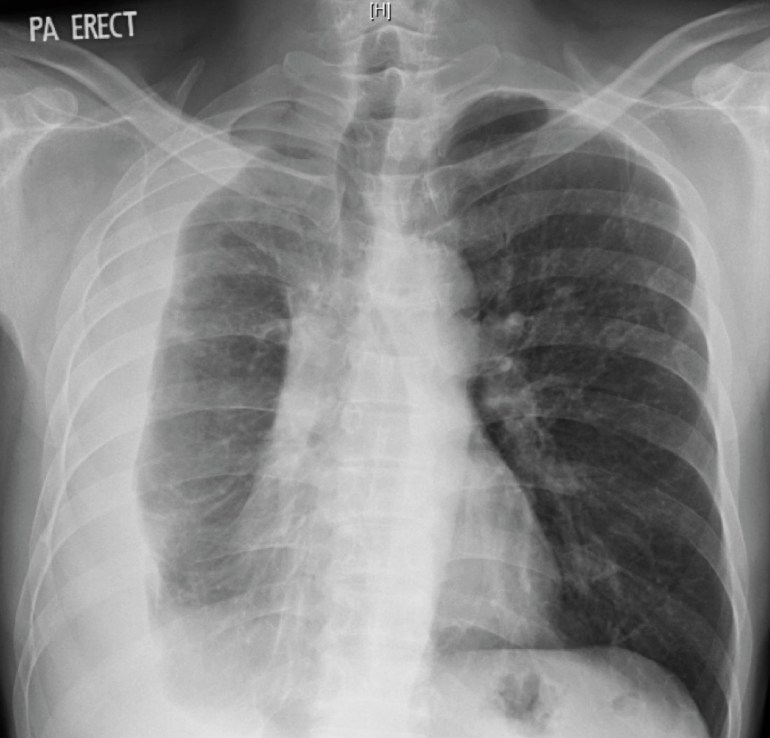

A middle-aged man who had renal transplantation 5 years ago (but otherwise well) presented with fever and shortness of breath for 2 weeks. He was found to have a right pleural effusion on chest X-ray, and underwent a diagnostic pleural tap. The TB PCR was positive from the pleural fluid, and he was started on standard anti-tuberculosis therapy (but with levofloxacin substituted for rifampicin owing to the interactions of the latter drug with other agents taken to maintain the renal transplant). The initial chest X-ray and the subsequent chest X-ray taken 10 days later are shown below.

Initial chest X-ray of the man with renal transplant, showing a right-sided loculated pleural effusion.